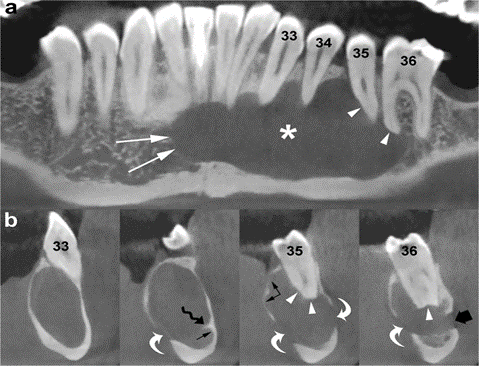

Panoramic (a) and cross-sectional (b) CBCT images show an OKC with well-defined and lobulated margins located in the interforaminal region of the mandible (asterisk). The lesion grows mesially by crossing the midline (white arrows). Note root resorption (arrowheads) and perforation of the cortices (curved arrows). Scalloping of the endosteal surface of the cortical plates (small black arrows) and small internal septum (wavy arrow) are also seen. Large black arrow, left mental foramen; 33, left canine; 34, left first premolar; 35, left second premolar; 36, left first molar